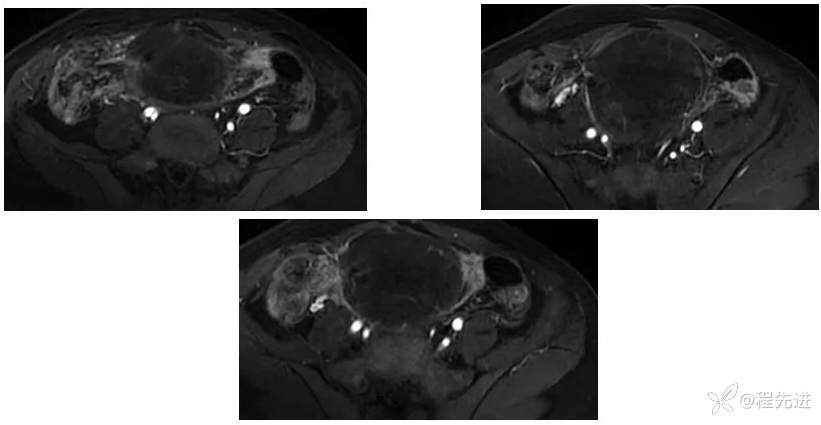

【腹盆】特别精彩病例|下腹痛20余天,男性病人腹腔巨大肿块该如何诊断

【患者信息】:男,41岁

【主诉】:下腹痛20余天

既往史:隐睾

肿瘤标志物:甲胎蛋白(AFP)>10000

增强: